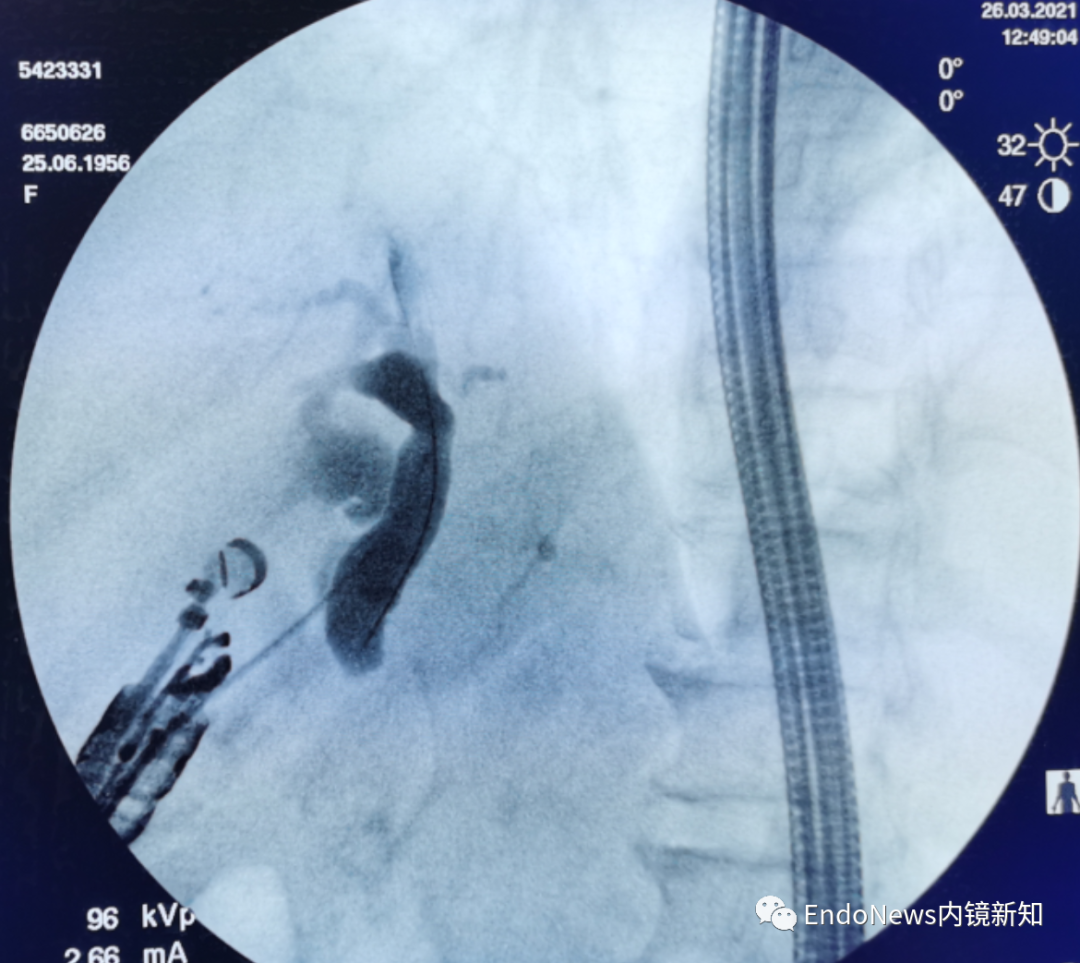

幸运的是,此患者第一针穿刺即成功,随后注射造影剂(EACP),显影后可观察到如图1(a)中所示,这个患者肝内胆管分支很多,但是由于每支均比较细,不容易找到理想的目标穿刺胆管。

下一步进入导丝之后,我们发现导丝朝向胆管上游(即肝缘方向,如图1(b)中所示),这时需要用到此前提到的调整方法:将穿刺针和导丝往回撤,尤其穿刺针,要撤入到肝实质内,但要注意导丝不能往回撤太多,这个过程一定要在X线下谨慎操作。

图1(a)

图1(b)